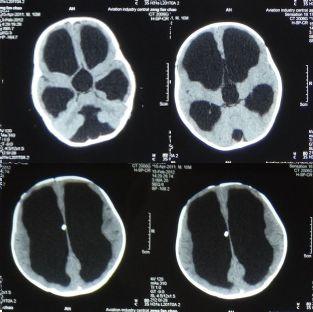

婴儿脑积水治疗的方法_头颅

术后3周复查头颅ct 治疗体会 火器性颅脑损伤在战争时期较常见,其

11个月婴儿感冒后发现竟有脑积水,治疗婴儿脑积水的好方法_头颅